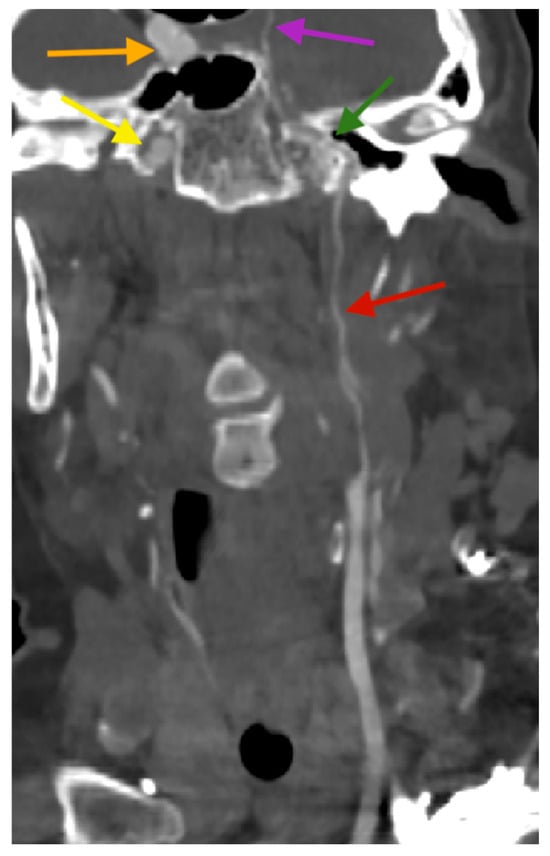

2. Case Report